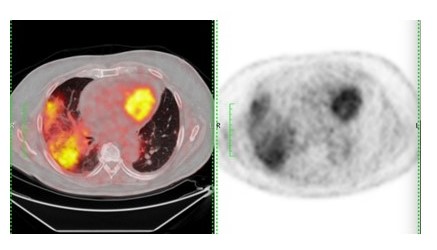

irAE: el papel de la imagen 18F-FDG PET/TC

Las manifestaciones radiológicas de los irAE se pueden encontrar en hasta el 17 % de los pacientes que reciben inmunoterapia, y esto puede preceder a las manifestaciones clínicas (32,33).

La 18F-FDG PET está evolucionando con varios puntos fuertes en la evaluación de la respuesta a la inmunoterapia tumoral. Se ha descubierto que mejoran el rendimiento discriminatorio y pronóstico (34).

Esto no lleva a que la 18F-FDG PET además de sus indicaciones clínicas basadas en la caracterización del microambiente inmune tumoral, 18F-FDG PET puede determinar otras características o parámetros que permiten obtener mayor información fundamental en el manejo del paciente oncológico (35) Cuadro 6.

Recientemente, el informe del simposio sobre inmunoterapia de la Asociación Europea de Medicina Nuclear indicó que se deben informar los hallazgos incidentales relacionados con irAE. Aunque los irAE pueden no estar necesariamente asociados con síntomas clínicos, los médicos deben ser conscientes de su presencia y garantizar un seguimiento clínico que, sin embargo, podría conducir a una intervención clínica (35).

Aunque es relativamente raro, la irAE más común en la región torácica es la inflamación pulmonar (neumonitis). A diferencia de otros irAE, es más frecuente con los medicamentos anti-PD-1 y con la terapia combinada (42). La neumonitis es muy variable en su inicio y gravedad: radioterapia pulmonar previa y la fibrosis son factores de riesgo para la neumonitis anti-PD-1 (27).

Los informes iniciales de neumonitis relacionadas con los inhibidores del punto de control inmunológico han descrito un espectro de manifestaciones radiológicas con diferentes patrones morfológicos de neumonías intersticiales (43,44).

En el tórax también se pueden observar linfadenopatía y granulomatosis similares a los sarcoides también se reconocen como un irAE, más comúnmente observado en los ganglios linfáticos mediastínicos e hiliares, El tiempo medio desde el inicio de la terapia fue de 3,2 meses (rango, de 0,2 a 9,1 meses) en pacientes con melanoma tratados con ipilimumab.. También se pueden observar cambios parenquimatosos pulmonares con engrosamiento nodular de los haces peribroncovasculares y el tabique interlobular. El muestreo histológico de estos casos reveló una inflamación granulomatosa en una distribución interlobular, peribronquiolar y subpleural que se asemeja a la sarcoidosis. Un informe reciente demostró que esta entidad también puede ocurrir como un hallazgo aislado en el pulmón, con un foco de consolidación pulmonar en ausencia de linfadenopatía o síntomas. Estos hallazgos se resuelven después de que se retengan los inhibidores del punto de control inmunitario (46,47).